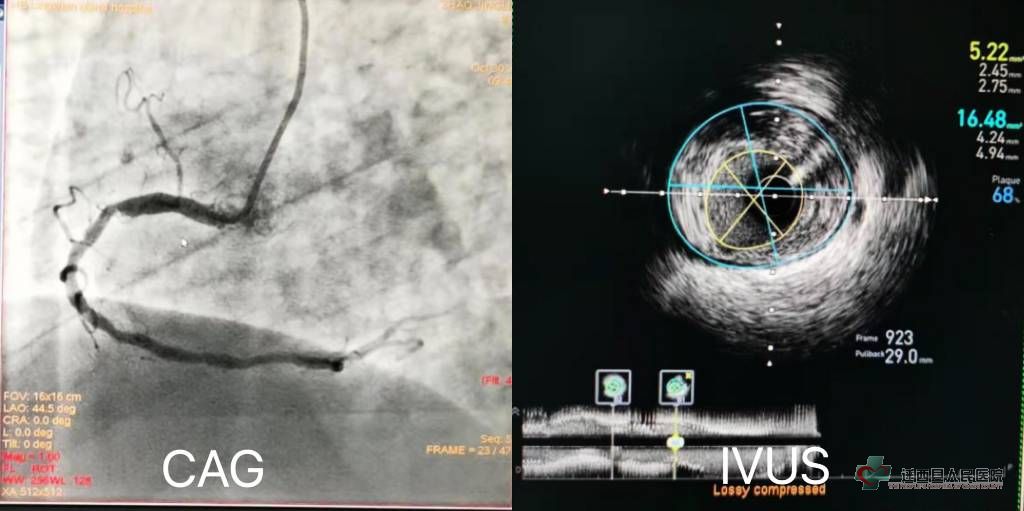

病例1:患者男性,69岁,阵发性心慌、胸闷、气短2小时入院。既往有高血压病、脑梗死病史。 冠脉造影:右冠全程弥漫性钙化性病变,近中段有两处相对固定的狭窄在60-70%之间,这样的病变会引起缺血症状吗?需要急着放支架吗?

术中经IVUS证实,患者右冠可见动脉粥样硬化斑块及脂质斑块,血管最重的斑块负荷达管腔面积68%,暂不需进行介入治疗。 病例2:患者男性,也是69岁,间断心悸、气短2年,加重伴呼吸困难2天,以“冠心病、心力衰竭”收入院,经规范的治疗心功能明显改善,住院期间患者反复发生卧位型心绞痛。